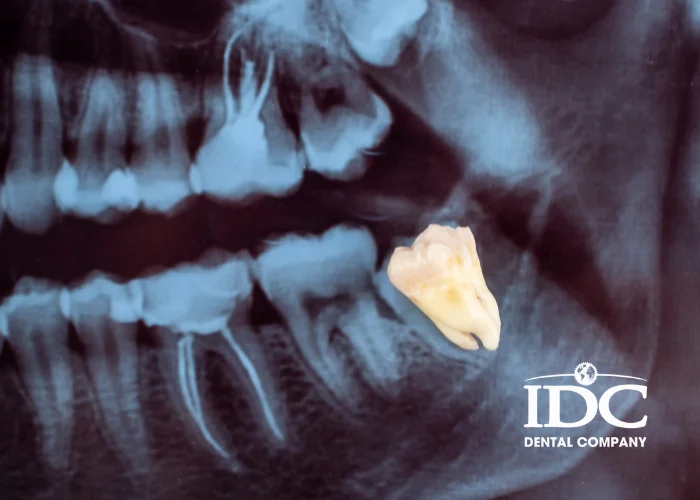

You should not remove wisdom teeth just by “feeling.” A cone-beam CT shows:

• The depth and direction of tooth growth

• How much the nerves are pressed

• Whether the root is very close to the sinus (upper wisdom tooth)

• Risk of bone infection or abscess

=>Using CT, the dentist can choose a safe technique and minimize risks.